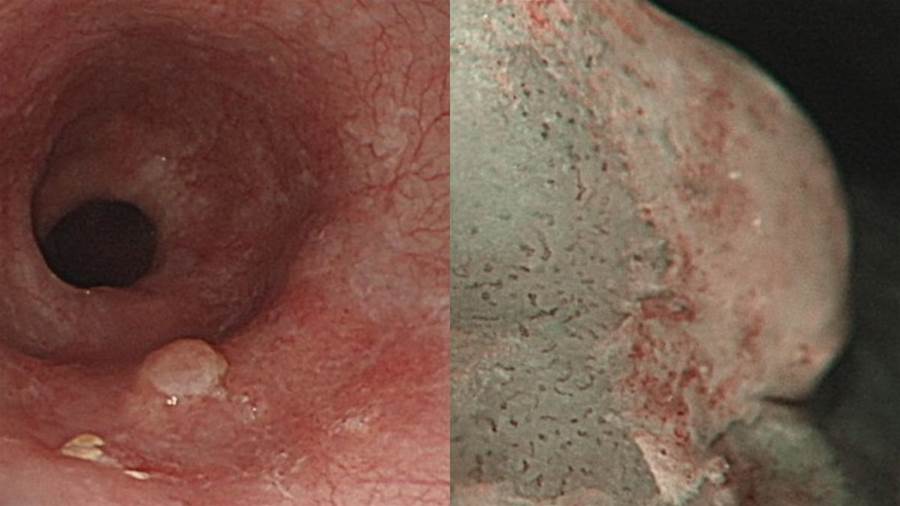

而戴男被發現胃食道逆流、胃潰瘍,且中段食道有一處約莫2公分、極不明顯暗紅病灶並合併有約0.

對此,蘇品碩解釋,在台灣大部分食道癌發現已是中晚期,僅有不到十分之一的食道癌患者,在初次診斷時是早期癌癥,早期食道癌幾乎不會造成任何身體不適,因此常被忽略,但當有吞嚥困難時,往往腫瘤已阻塞食道60%以上,另外少數可能會有胸痛、吐血、黑便、咳嗽、聲音沙啞。